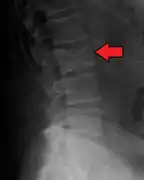

The diagnostic examination of a person with suspected multiple myeloma typically includes a skeletal survey. This is a series of X-rays of the skull, axial skeleton, and proximal long bones. Myeloma activity sometimes appears as "lytic lesions" (with local disappearance of normal bone due to resorption) or as "punched-out lesions" on the skull X-ray ("raindrop skull"). Lesions may also be sclerotic, which is seen as radiodense.[70] Overall, the radiodensity of myeloma is between −30 and 120 Hounsfield units (HU).[71] Magnetic resonance imaging is more sensitive than simple X-rays in the detection of lytic lesions, and may supersede a skeletal survey, especially when vertebral disease is suspected. Occasionally, a CT scan is performed to measure the size of soft-tissue plasmacytomas. Nuclear Medicine Bone scans are typically not of any additional value in the workup of people with myeloma (no new bone formation; lytic lesions not well visualized on nuclear bone scan).

- Pathological fracture of the lumbar spine due to multiple myeloma